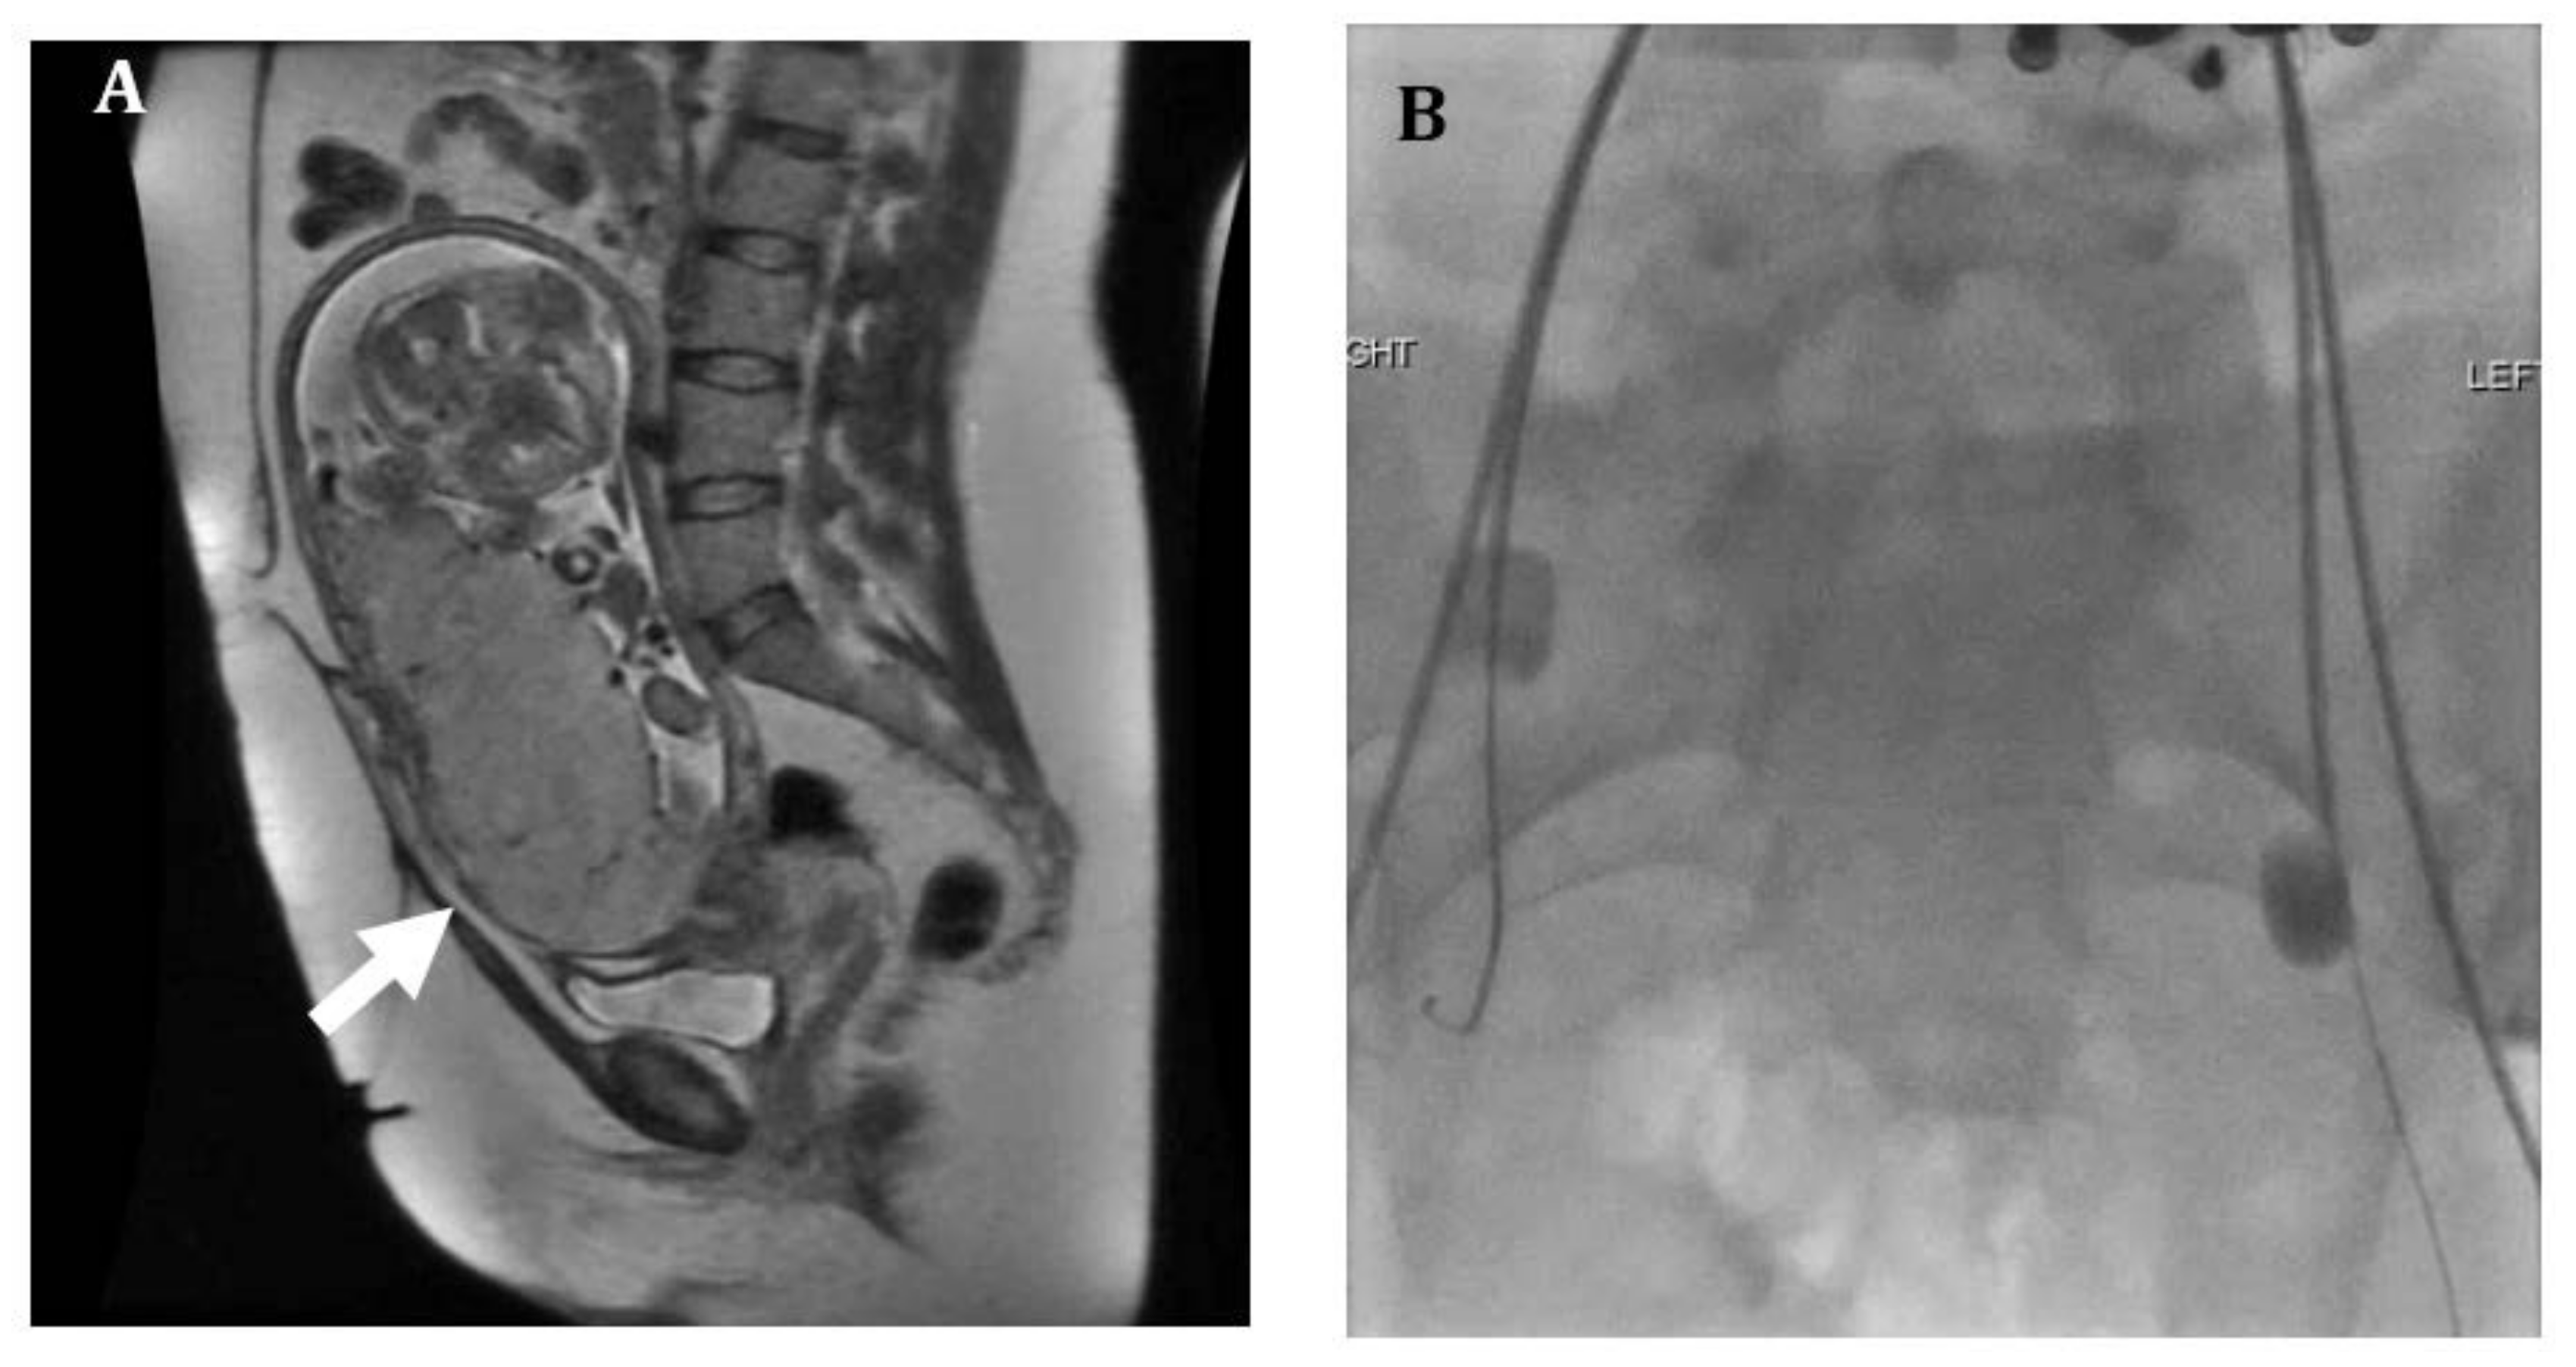

Figure 2.

Thirty-six-year-old female with placenta increta. (A) Sagittal T2 Half-Fourier-Acquired Single-shot Turbo spin Echo (HASTE) magnetic resonance (MR) image shows a bulging placenta at the lower uterine segment (arrow) with disorganized architecture, suggestive of placenta increta. Complete placental previa as well as an omphalocele were also noted. (B) Prophylactic bilateral internal iliac artery occlusion balloons were placed prior to cesarean hysterectomy. Patient underwent cesarean hysterectomy at 22 weeks with delivery of a demised fetus. Patient required extensive lysis of adhesions between the lower uterine segment and bladder.